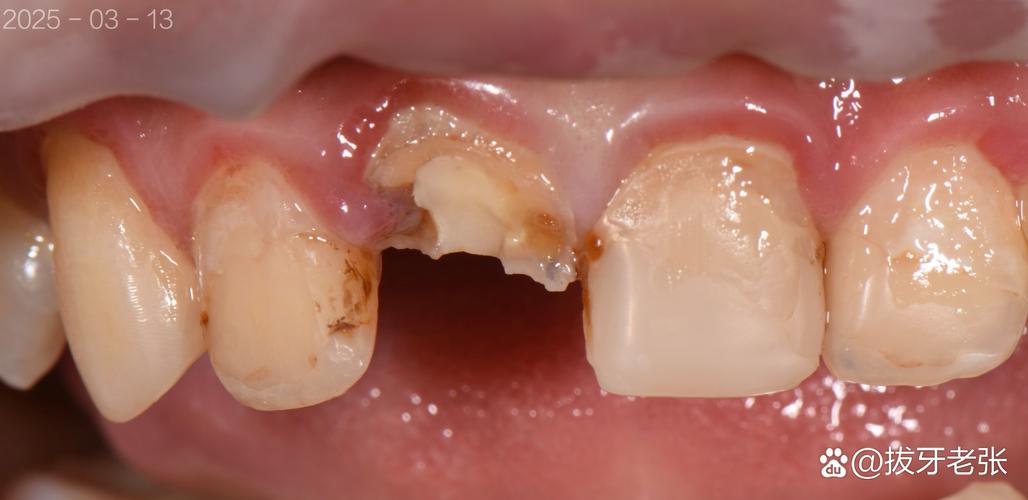

(图片来源网络,侵删) -

牙龈组织变化:

种植体周围牙龈在术后愈合过程中,如果发生退缩(recession),原本覆盖在基台上的牙龈变少了,会暴露出基台的一部分,同时牙冠边缘位置可能显得更低,视觉上感觉牙冠高度不够,或者,牙龈增生覆盖过多,也会显得牙冠矮小。